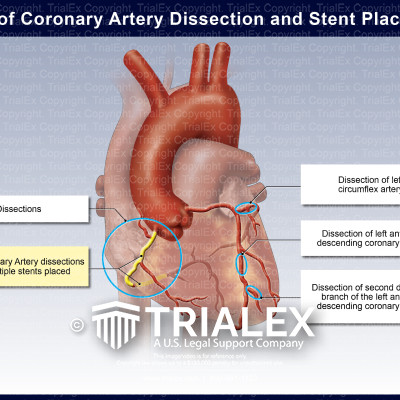

Figure 2 from A Large Isolated Congenital Left Circumflex Artery-to …

Isolated hypoplastic circumflex coronary artery: a rare cause of …

Right Coronary Artery and Left Circumflex Artery Stent Placements …

Sites of Coronary Artery Dissection and Stent Placement – TrialExhibits …